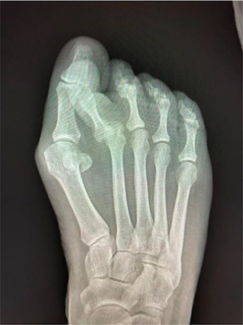

For larger bunions, surgeons can effectively use the Lapidus to correct deformities in the sagittal and frontal planes. These authors examine the literature to see if minimally invasive surgery (MIS) has evolved enough to be as effective.